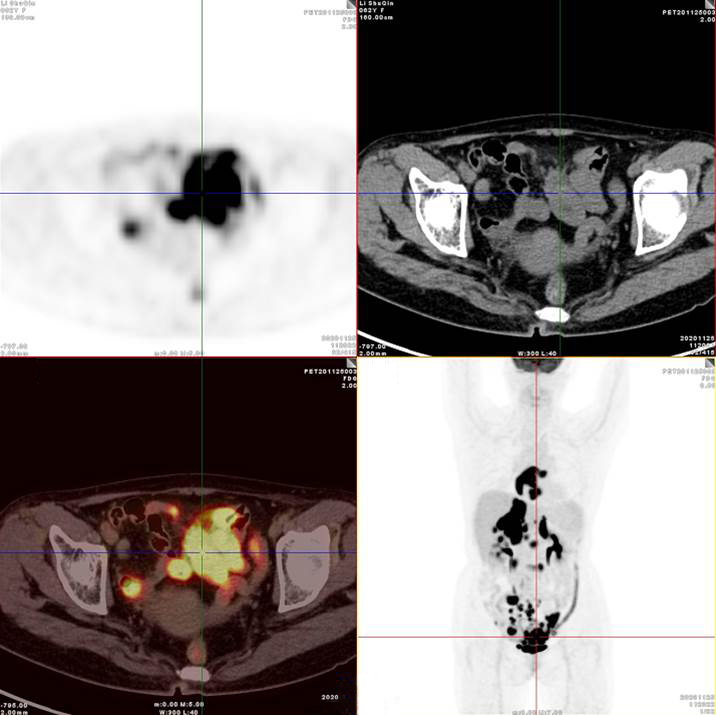

PET/CT影像圖

腸系膜多發(fā)淋巴結(jié)放射性攝取增高

多段小腸腸管放射性攝取增高

影像診斷

考慮淋巴瘤,請結(jié)合臨床病理